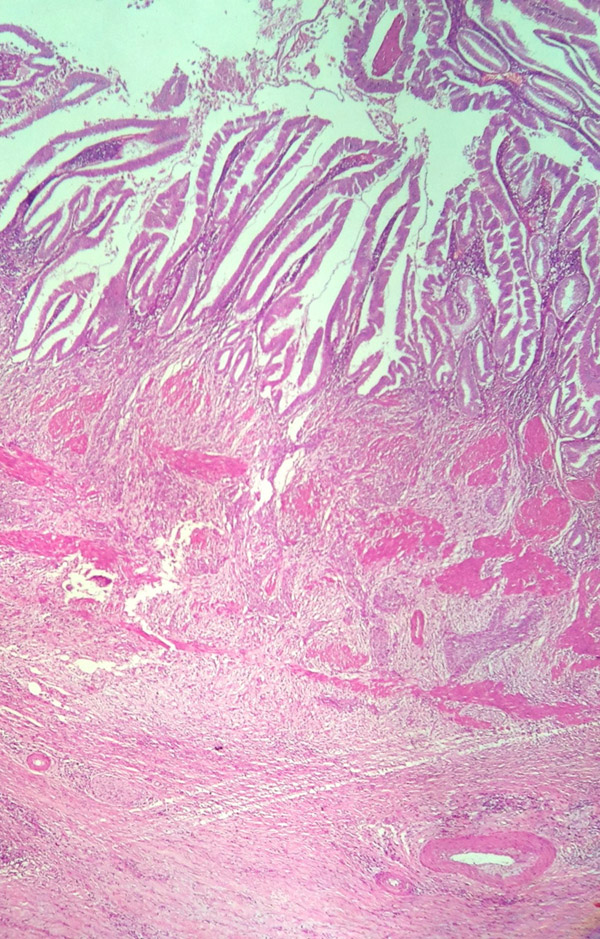

Adeno Carcinoma Gall bladder

Histology showing Gallbladder adenocarcinoma

Histology showing Gall bladder Adenocarcinoma infiltrating the liver